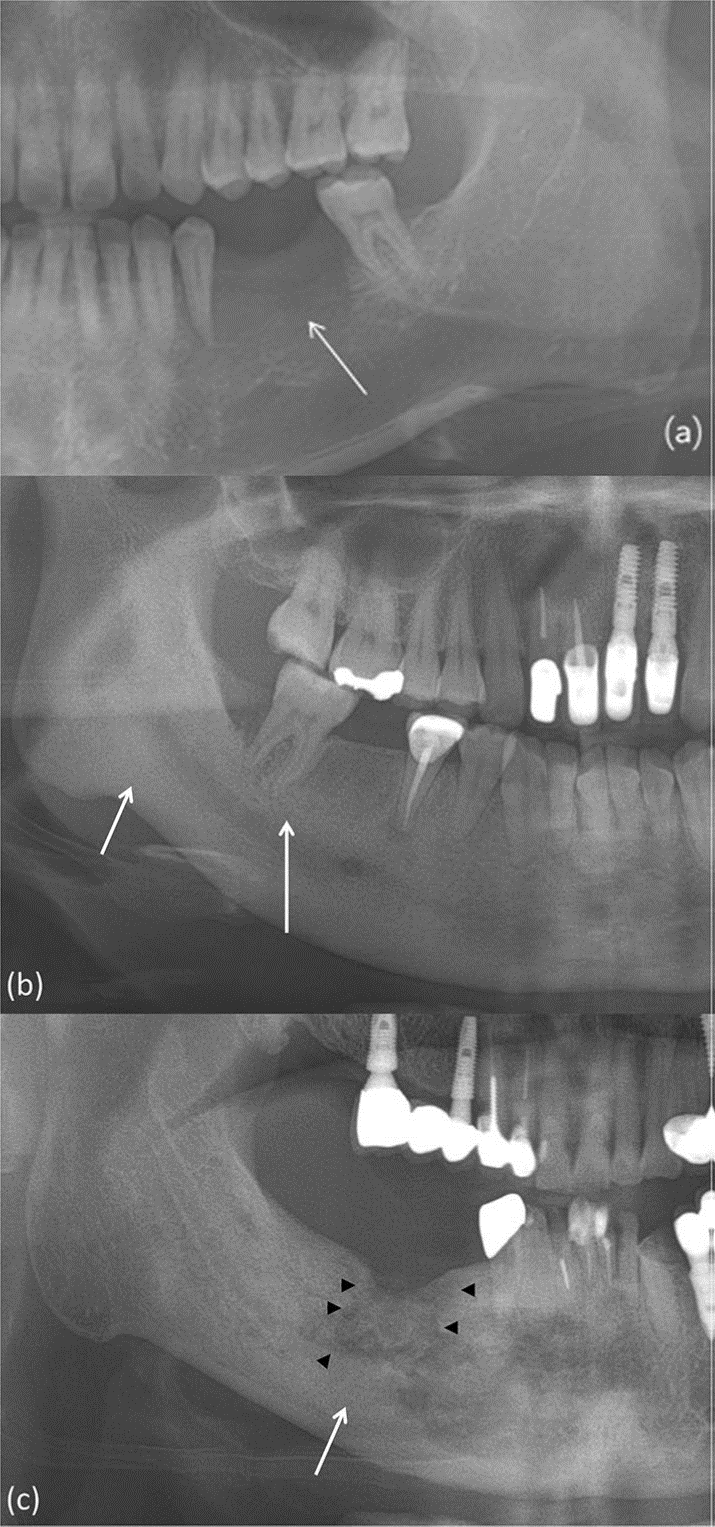

En las radiografías panorámicas, se pueden observar diferentes patrones de las lesiones y se clasifican como osteolítico, esclerótico o mixto. Se evaluó la presencia de secuestros, formación de hueso perióstico nuevo, afectación del hueso cortical y afectación del canal mandibular. Se analizaron los cambios en los tejidos duros en las imágenes de tomografía computarizada. Estos cambios en los tejidos duros incluían la presencia de defectos trabeculares y corticales, esclerosis, secuestros y formación de hueso nuevo periótico. Los secuestros se clasificaron como trabeculares, corticales, mixtos trabeculares y corticales o incompletos. Además, el patrón de hueso nuevo perióstico se clasificó como laminar continuo, laminar interrumpido y sólido. Las imágenes de tomografía computarizada se evaluaron para detectar cambios en los tejidos blandos, como inflamación, celulitis, tejido de granulación, sinusitis o mucositis, abscesos, miositis y fístulas.